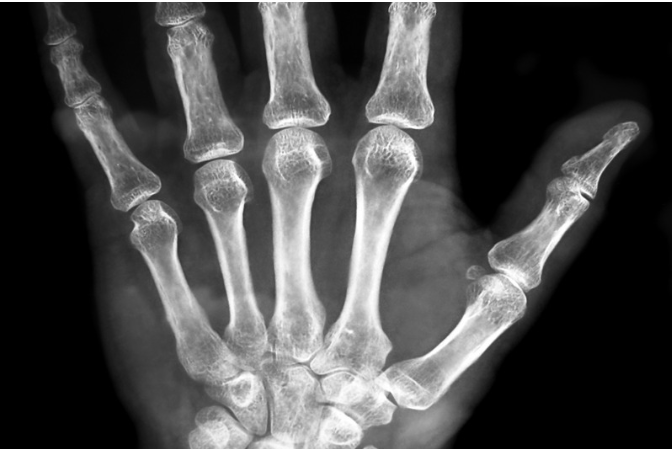

手・指のお悩み